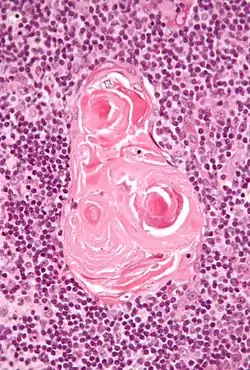

In the medulla, the network of epithelial cells is coarser than in the cortex, and the lymphoid cells are relatively fewer in number.[1] Concentric, nest-like bodies called Hassall's corpuscles (also called thymic corpuscles) are formed by aggregations of the medullary epithelial cells.[3] These are concentric, layered whorls of epithelial cells that increase in number throughout life.[1] They are the remains of the epithelial tubes, which grow out from the third pharyngeal pouches of the embryo to form the thymus.[6]

- Micrograph showing a Hassall's corpuscle, found within the medulla of the thymus.